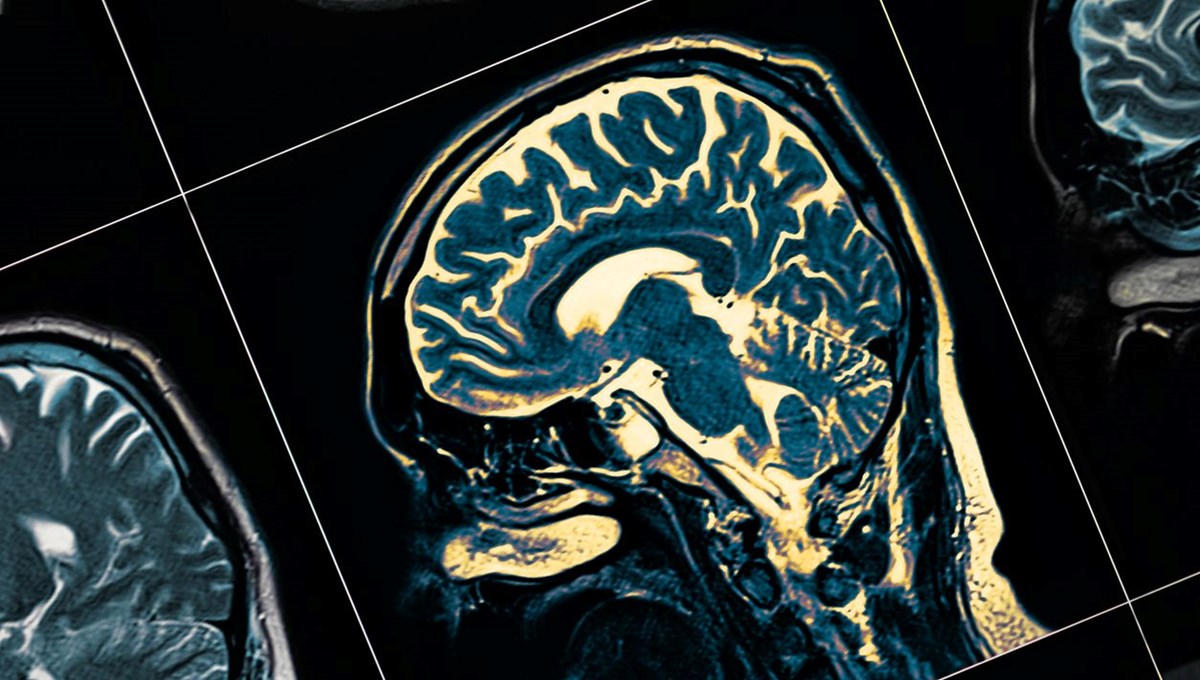

Son yıllarda yaygın bir demans türü haline gelen Alzheimer hastalığı; düşünce, davranış ve bellek fonksiyonlarındaki değişimi ifade eder. Uzmanlar, bazı mesleklerin, Alzheimer hastalığına yakalanma riskini azaltabildiğini öne sürüyor.

Yapılan son çalışmaya göre, taksi ve ambulans şoförlüğü yapmak, beyinde hafıza ve yön duygusuyla bağlantılı olan hipokampüsü, Alzheimer’ın etkilerine karşı daha dirençli hale getiriyor. Konuyla ilgili yapılan önceki araştırmalar da, taksi ve ambulans şoförlerinin hipokampüslerinin yaşlandıkça gelişmeye devam ettiğini göstermişti.

Londra Üniversitesi’nde yapılan bir önceki çalışmada da taksi şoförlerinin beyinlerindeki mekansal muhakeme ve hafızadan sorumlu bölgenin, diğer meslek gruplarına göre daha gelişmiş olduğu tespit edilmişti.

Uzmanlara göre, taksi ve ambulans şoförlerinin beyinlerindeki bağlantının güçlenmesi, Alzheimer sürecine karşı daha dirençli olmalarını sağlıyor olabilir. Bilim insanları, konuyla ilgili net bir veriye ulaşılması için daha fazla araştırmaya ihtiyaç duyulduğunu belirtiyor.